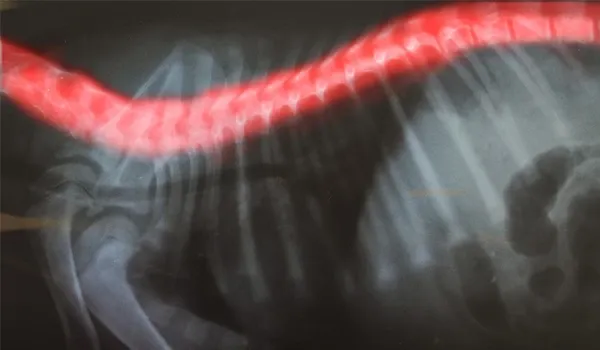

- X-rays and perhaps a CT (computed tomography) or MRI (magnetic resonance imaging) scan of your dog's spine

Diskospondylitis causes inflammation (itis means inflammation), swelling, and bone deformities that put pressure on or compress the spinal cord that runs through the vertebrae of the back.

Diskospondylitis, or DS, is an infection within a dog's back that is located within the disk and the adjacent vertebrae. When a bacterial pathogen — or, much less frequently, a fungus — settles within a disk and on either side of the vertebrae, diskopondylitis is the result.

Any disk in the spine can be affected, but the infection is most often seen in disks in the lower back (lumbosacral region).